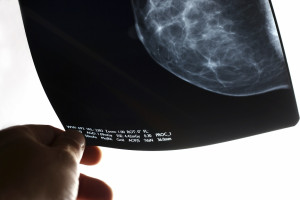

“Dense breast tissue appears white on a mammogram, and so do tumors and other abnormalities, which makes it easier for tumors to hide. Although mammograms can still be effective for women with dense breasts, detecting calcifications for example, this camouflaging does make it more difficult to detect some cancers,” explains John Stassi, MD, radiologist with The Barbara Brodsky Comprehensive Breast Center at Bryn Mawr Hospital, part of Main Line Health.